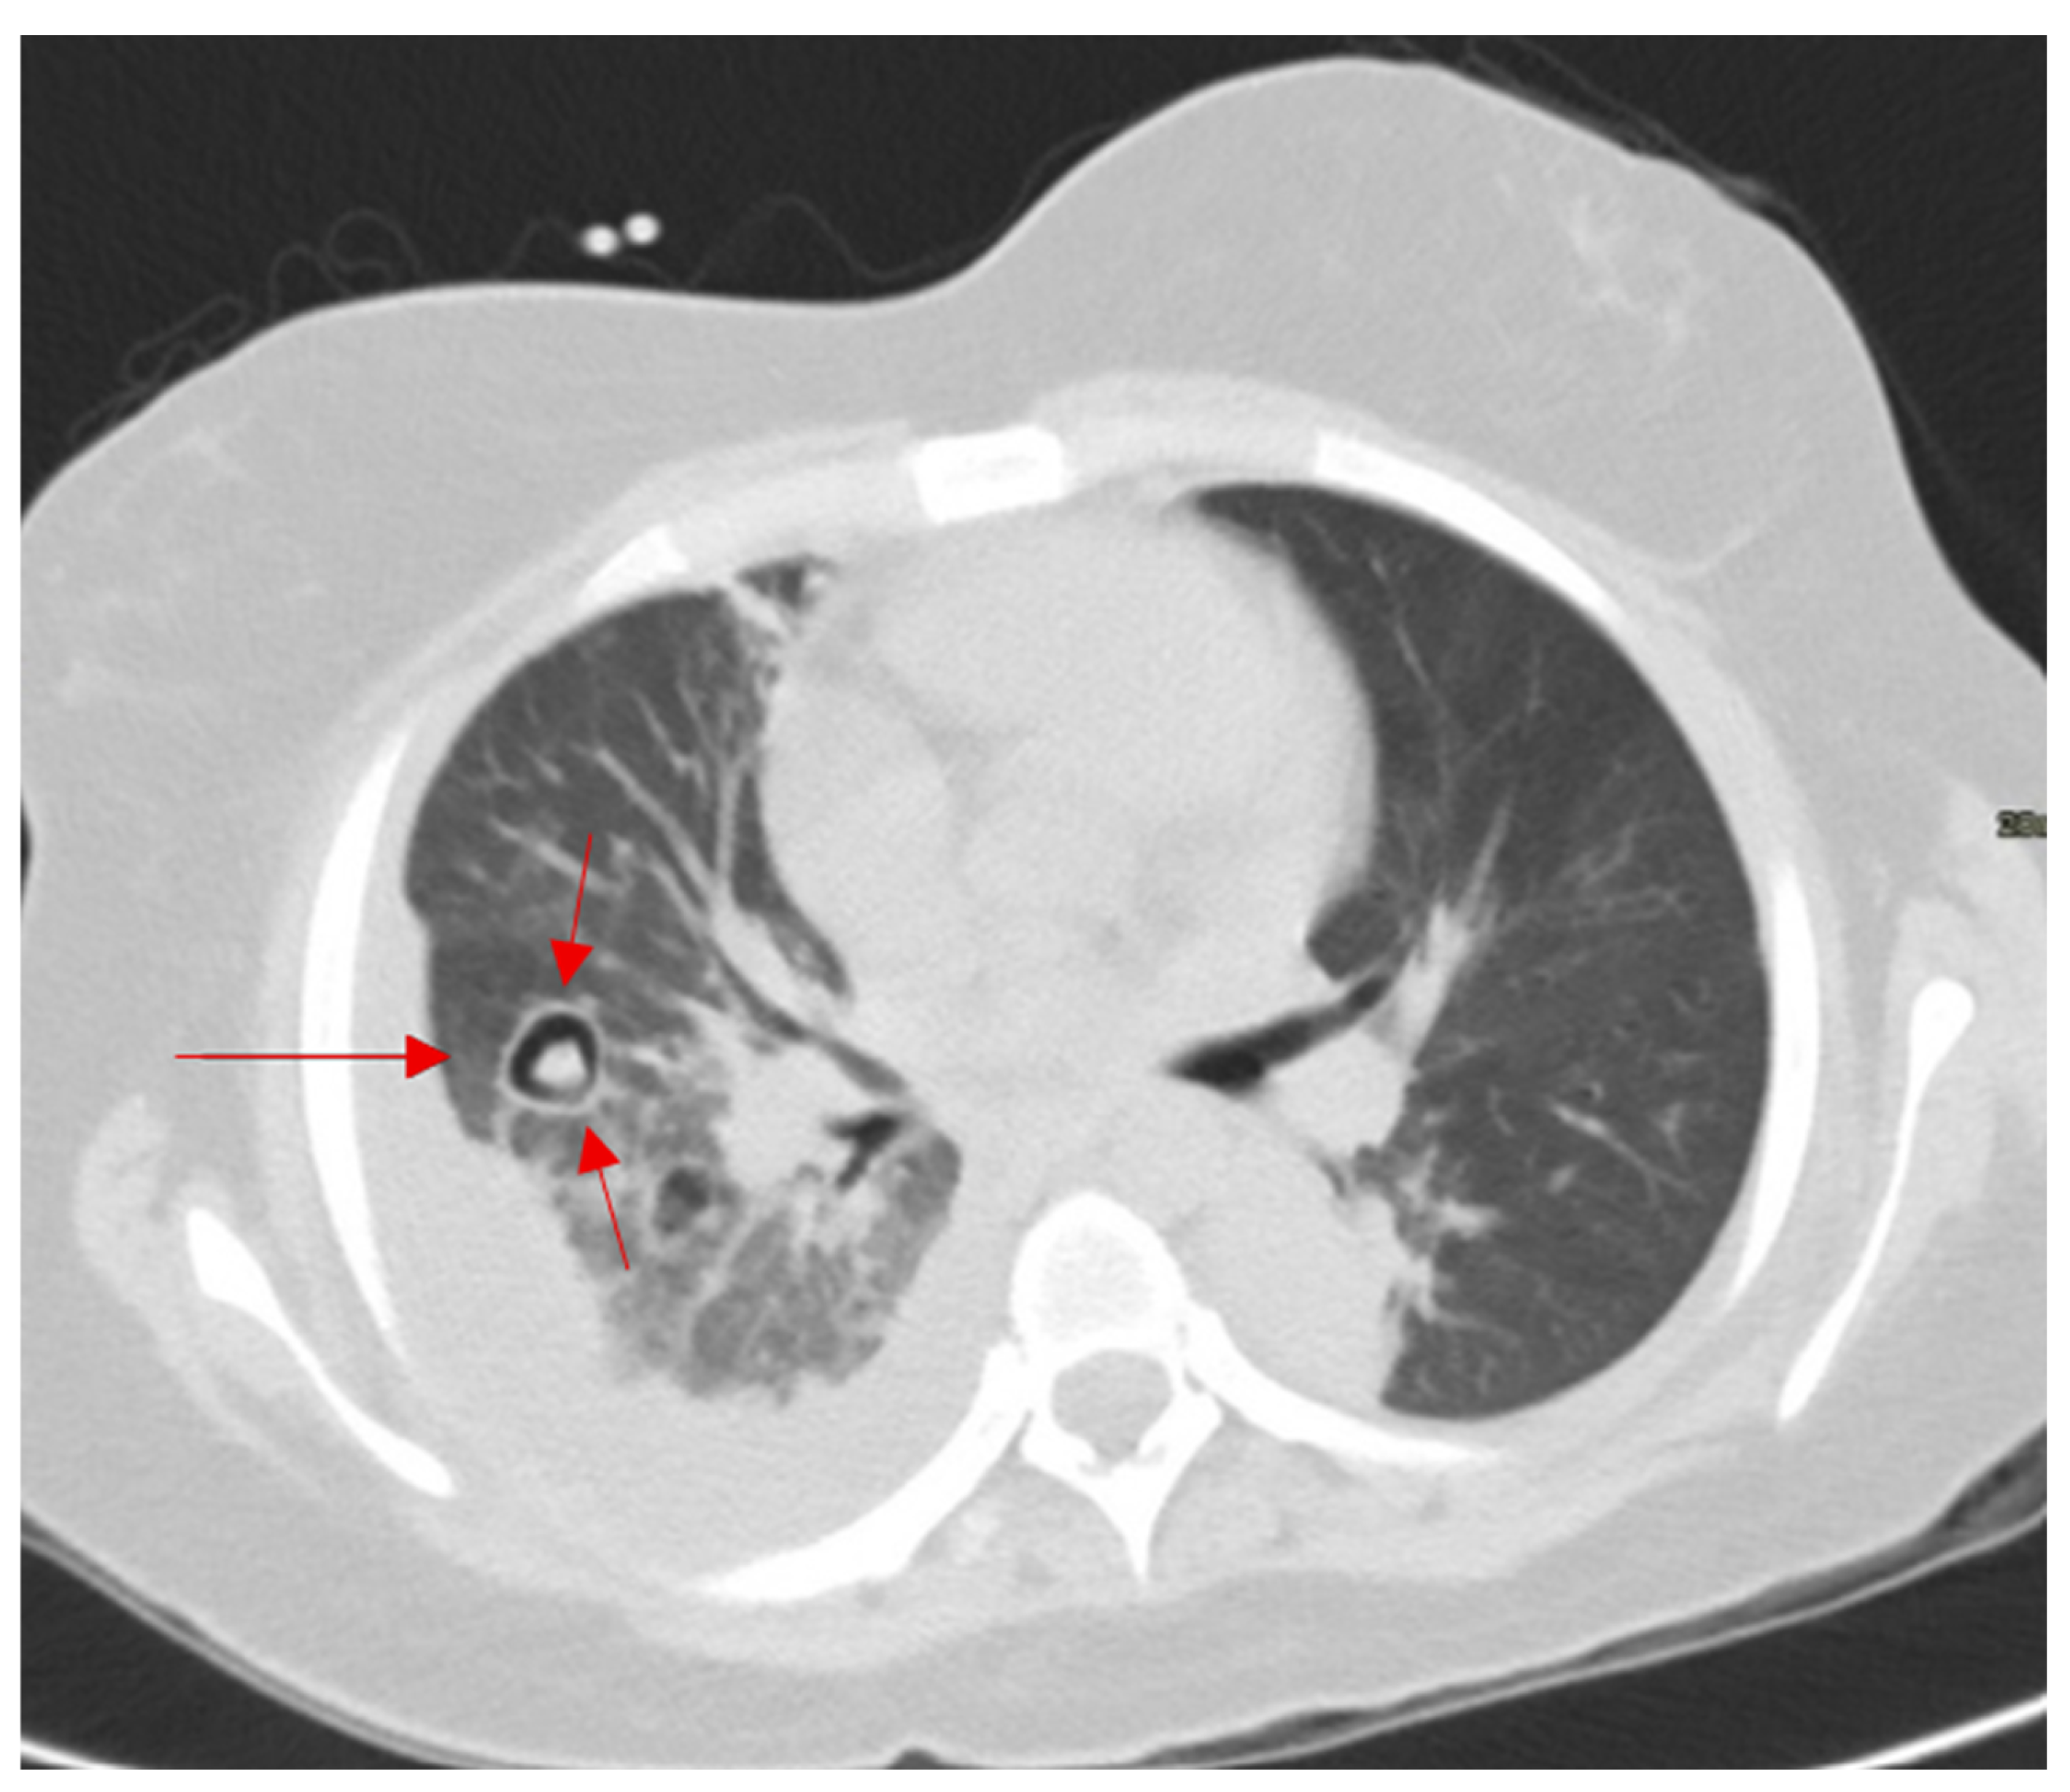

2.15. Halo Sign

- Abramson, S. The Air Crescent Sign. Radiology 2001, 218, 230–232. [Google Scholar] [CrossRef] [PubMed]

- Sharma, S.; Dubey, S.K.; Kumar, N.; Sundriyal, D. ‘Monod’ and ‘air crescent’ sign in aspergilloma. BMJ Case Rep. 2013, 2013, bcr2013200936. [Google Scholar] [CrossRef] [PubMed]

- Tseng, Y.Y.; Chen, C.H. Air crescent sign: Not always due to fungal infection. QJM 2015, 108, 255–256. [Google Scholar] [CrossRef] [PubMed][Green Version]